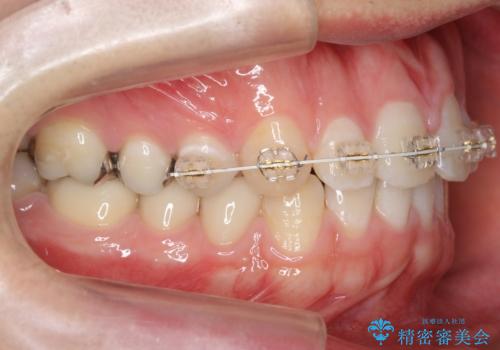

前歯のねじれ 上だけ部分矯正でコストダウン

- 前歯のねじれを部分矯正で治療しました。

奥歯のかみ合わせを変えずに、費用を抑えて短期間に治療したい方におすすめです。

奥歯のかみあわせも問題なく、また、下の前歯のがたつきが元からない場合は上の部分矯正が十分可能です。